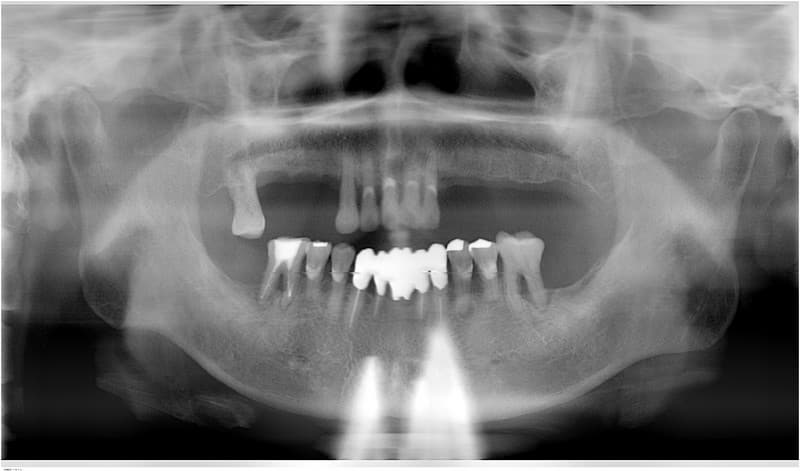

完全に歯がない場合

従来の治療

土台になる歯がないため総入れ歯となります。

うまく合わない場合は、食事がおいしくない、うまく話せない、外れやすいなどの問題が生じることがあります。

インプラント治療

インプラントを土台にして入れ歯を安定させ、動かず、しっかりした義歯にすることが出来ます。

また、あごの状態によってはインプラントによって一本ずつの歯を自然な状態で再建することも可能です。